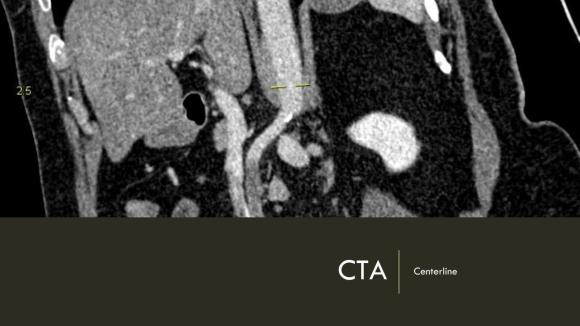

Arteriography from femoral access showed an occlusion of the SMA beyond the middle colic artery, a typical pattern for an embolism that occurs when embolism lodges distally and propogates proximally (image below).